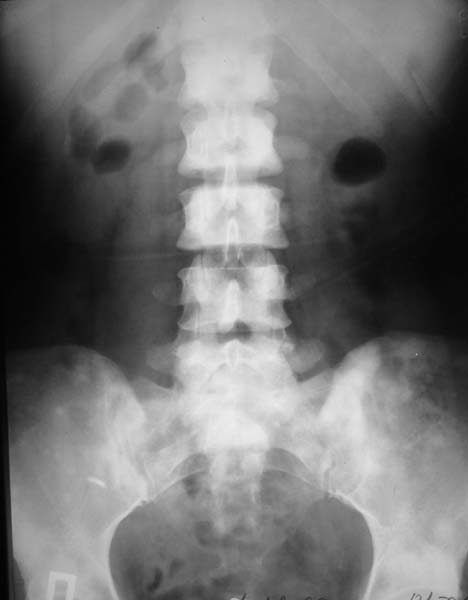

Женщина, 46 лет.

В течение четырех месяцев жалобы на боли в спине.

При МРТ (29.10.06) обнаружены диффузно-очаговые изменения в пояснично-крестцовом отделе позвоночника предположительно вторичного характера.

В октябре 2006 г. по поводу маточного кровотечения (менопауза 4 мес.) выполнено УЗИ - гиперплазия эндометрия, полипоз. Операция - удаление полипа, выскабливание полости матки. Цитологический анализ - пласты переходного климактерического эндометрия.Проведено комплексное исследование. В приложении: рентгенограммы и томограммы поясничного отдела позвоночника; радиологические исследованиямолочной железы, ЖКТ, почек, грудной клетки, анализы.УЗИ (18.12.06.) щитовидной железы, молочных желез - без патологии (умеренный фиброз по ходу млечных протоков).

Остеосцинтиграфия 4.12.06. - активный остеобластический процесс в поясничном, нижнегрудном отделах позвоночника, костях таза.Местными онкологами онко-процесс исключен. Фтизиатрический и онкогематологический диагнозы исключены.

Вопросы: 1. Диагноз? 2. Методы дополнительной диагностики? 3. Тактика лечения?